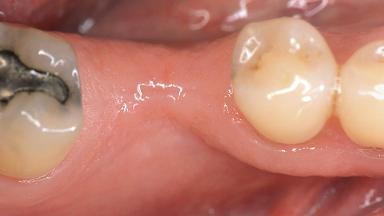

Soft-Tissue Volume Augmentation Using a Connective-Tissue Graft Harvested from the Maxillary Tuberosity

Jaw Mandible

Area Posterior

# of Teeth 1

# of Implants 1

Soft Tissue Grafting Simultaneous